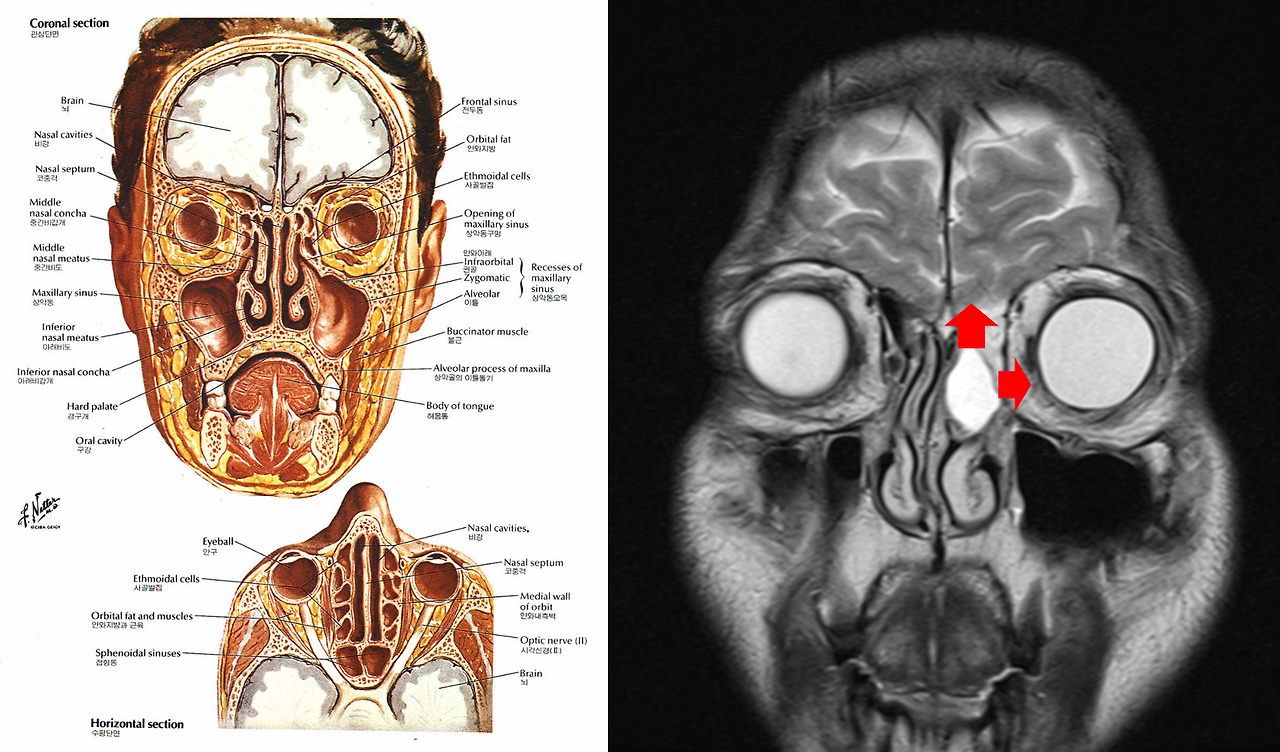

코 안, 즉 부비강 수술은 비교적 안전하고 쉬운 수술에 속한다. 다만 혹 위로는 뇌가 있고, 옆으로는 눈이 있다. 수술하다 뇌와 경계를 이루는 뼈를 부수면 뇌척수액이 흘러나올 수도 있고, 눈과 경계를 이루는 뼈를 부수면 눈의 움직임이 이상해질 수도 있다. 거기다 점액낭종(mucocele)은 악성 암이 아니라, 양성 혹이지만 100% 확신하기는 어려웠다. 악성 종양일 수도 있었다.